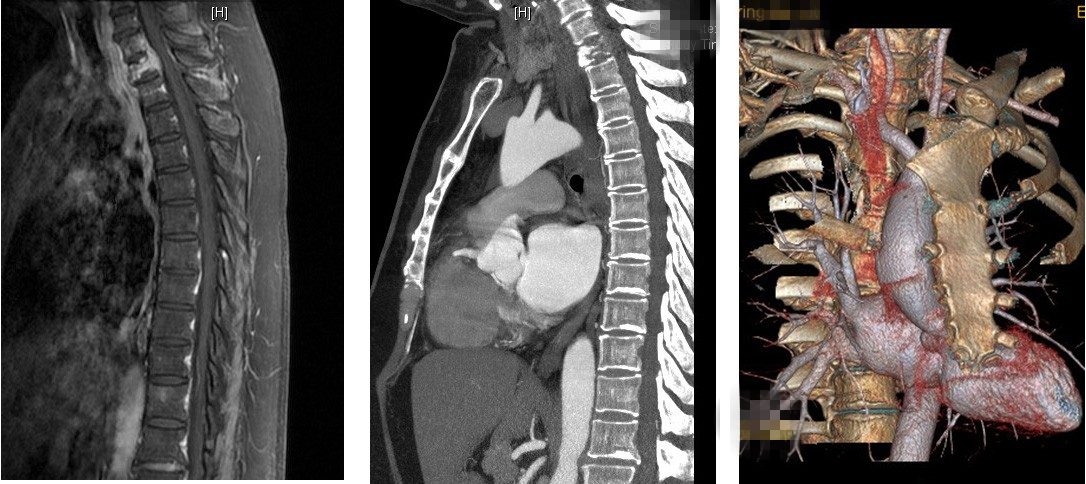

清华长庚医院11月08日电(神经外科 孙振兴、杨峰、荆林凯)近日,北京清华长庚医院接待了一位来自山东罹患乳腺癌的患者于女士。在乳腺癌根治术14个月后,于女士出现胸背部疼痛、左上肢麻木等症状,MRI检查发现胸椎多个椎体信号异常,初步诊断为乳腺癌转移、T1椎体病理性骨折。

患者部分术前影像资料